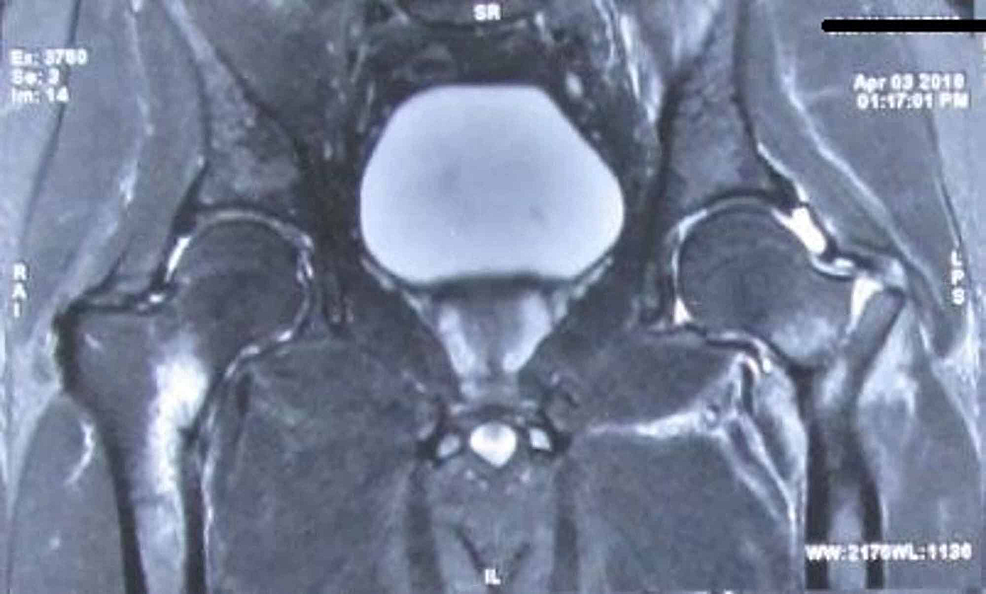

From radiopaedia.org

Image Lower Femur Stress Fracture • stress fractures indicate bone fatigue or insufficiency or a combination of these. A stress fracture is the final stage of a stress injury and occurs if the bone fails to withstand a repetitive, cumulative loading force and is no longer capable of mitigating that. Although quite rare, it is caused by prolonged overuse. Pain develops gradually as a dull. Lower Femur Stress Fracture.